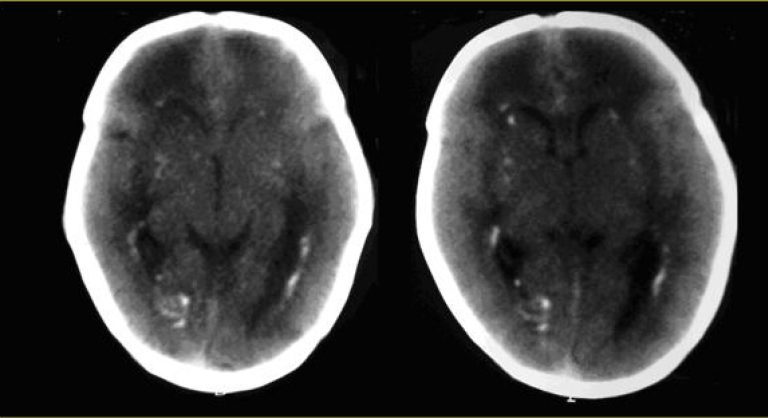

Recém-nascido com idade gestacional de 37 semanas e 2 dias, de parto normal, do sexo feminino, admitido em Unidade de Terapia Intensiva Neonatal (UTIN) em dia 11 de Julho de 2009. Pesava 2.030 g; estatura 41,0 cm; perímetro cefálico 31,0 cm; boletim Apgar 8, 9 e 9, no 1°, 5° e 10° minutos, respectivamente. Teve como hipótese diagnóstica na admissão toxoplasmose congênita, devido à história materna (sorologia para toxoplasmose IgG positiva e IgM positiva com avidez de 85% no primeiro trimestre do pré-natal). A ultrassonografia (US) gestacional morfológica do primeiro trimestre mostrava calcificações intracranianas. O recém-nascido apresentava restrição de crescimento intrauterino, esplenomegalia, petéquias e plaquetopenia. Introduziu-se tratamento para toxoplasmose com sulfadiazina, pirimetamina e ácido folínico. A tomografia de crânio mostrou múltiplos focos de calcificações periventriculares bilaterais e nos núcleos da base. Devido a esses achados, foi pedida sorologia para citomegalovírus na mãe e na criança, cujos resultados foram os seguintes: na puérpera, IgM não reagente, IgG reagente; no recém-nascido, IgM e IgG reagentes. Realizadas pesquisas para células de inclusão ctitomegálica na urina do recém-nascido e reação em cadeia da polimerase (PCR), com resultados positivos. O recém-nascido recebeu alta hospitalar sendo encaminhado para ambulatório para receber tratamento com ganciclovir.

As infecções congênitas, sífilis, toxoplasmose, rubéola, citomegalovirose e herpes, que correspondem ao acrônimo STORCH, podem se caracterizar por sintomas comuns: restrição de crescimento intrauterino; hepatoesplenomegalia; icterícia com aumento de bilirrubina direta; anemia; petéquias; lesão de pele e mucosas; encefalite; pneumonia e trombocitopenia(,). Para diagnóstico das STORCH, sorologia com pesquisa de IgM e IgG, PCR e exames de imagem, são os métodos mais comuns. Na toxoplasmose o quadro é composto principalmente por hidrocefalia ou microcefalia, calcificações cerebrais difusas no córtex cerebral, microftalmia e coriorretinite (associada à microcefalia)(). A citomegalovirose apresenta-se com calcificações periventriculares e, ao exame de fundo de olho, coriorretinite não associada à microftalmia. O herpes pode ser identificado pela presença de herpes genital materno atual.